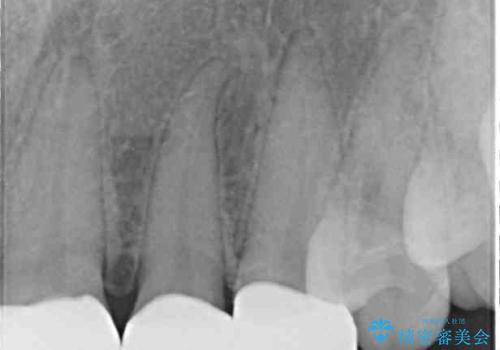

- 前歯の歯並びと虫歯を気にして来院された患者様です。

上下前歯の歯列不正はインビザラインにより歯列を整え、その後に、前歯5本をオールセラミッククラウンにて補綴治療することとしました。

矯正治療前に前歯のむし歯治療を行ったものの、樹脂で充填するには虫歯が広範囲であったため、審美的に問題がありました。

矯正治療にて歯並びを整えた後に、虫歯の大きかった5本の歯をセラミッククラウンにて補綴し、明るい口元になりました。